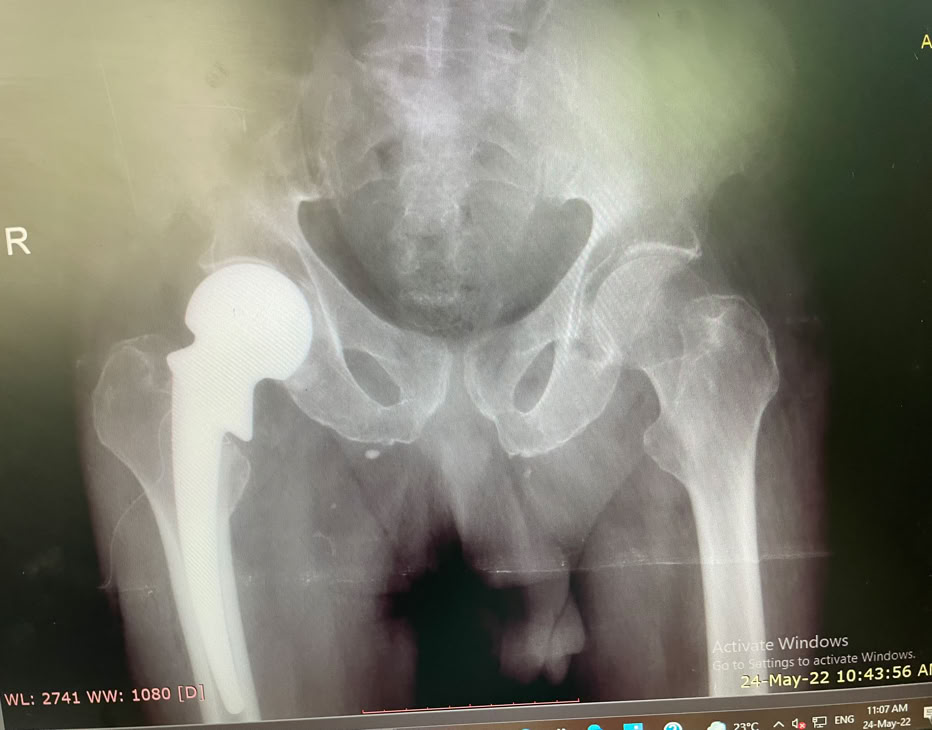

Nada más llegar, pase de visita para ver como empezar a programar las intervenciones de la semana. No había muchos pacientes ingresados pendientes de cirugía, pero no tuvimos que esperar mucho rato para recibir una herida por arma de fuego en un pie y una fractura de cadera de un paciente trasladado de un hospital de los Hermanos de San Juan De Dios que tratan enfermos de Lepra.

Ambos se resolvieron el lunes por la mañana con una prótesis parcial de cadera y el disparo en el pie con una cirugía de desbridamiento, limpieza y cierre.